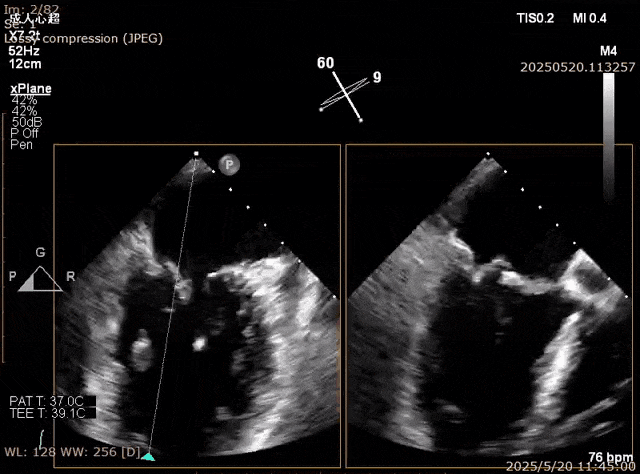

在经股静脉途径的TEER手术时,房间隔穿刺是一个很重要的基础步骤。有时候房间隔组织较韧较厚(多见于房间隔短穿刺位置需要靠后,或者外科房间隔修补术后),穿刺针通过之后要通过导引大鞘(GC)存在着较大困难,若强行推送大鞘可引起房间隔撕裂到左心房顶引起灾难性心包填塞。传统做法时使用外周球囊对房间隔进行扩张,但是不是每个导管室都常规配备外周球囊,且使用过大球囊仍可引起房间隔撕裂风险。我们提供了一种更简洁的方式,即使用导引鞘内芯和房间隔穿刺鞘两个管子(双管齐下)同时扩张房间隔穿刺口,再推送导引大鞘通过房间隔,无需额外器械,操作简单高效且安全(图1-4)。

图4. 顺利送入导引鞘通过房间隔